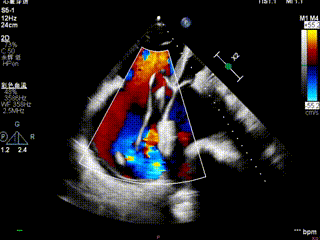

第二枚夹子释放后血流

送入第二枚SW0609(短宽型)二尖瓣夹,使其紧贴第一枚夹子。在食道心脏超声三维多平面重建(3D-MPR)引导下,将夹子跨瓣送入左心室。首次尝试捕捞并夹持瓣叶后关闭夹子,外侧反流量仍较多;随后反转夹子并重新捕捞夹持成功,此时前后叶活动均受限,外侧反流显著减少。释放夹子后,三维超声显示组织桥稳定,反流减轻至轻中度,平均跨瓣压差未见狭窄征象,肺静脉逆流亦有所改善。